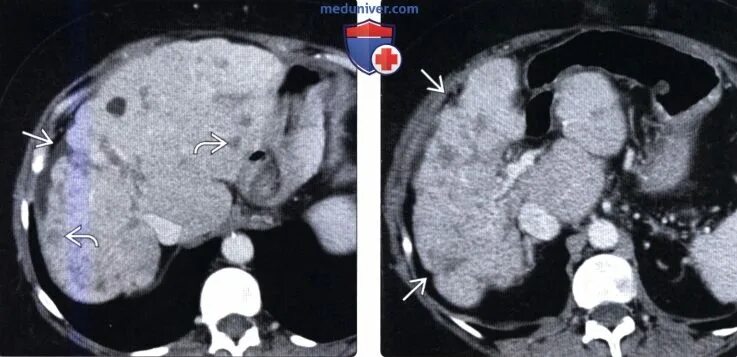

Как отличить метастазы